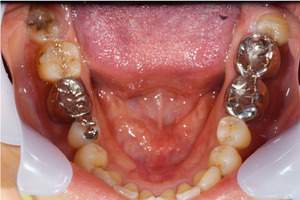

患者様の初診時レントゲン写真

【担当医師所見】

咬合平面の整頓の必要性 有

交叉咬合、オーバージェットの是正

歯周病の治療の必要性

ブラッシング方法の教授

左右上下合わせて4本の抜歯を行った